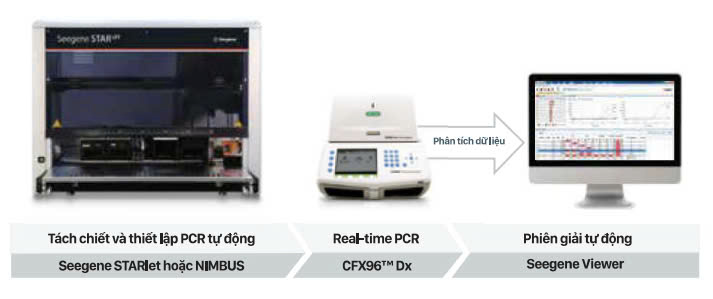

1. Các bệnh lý đường hô hấp ảnh hưởng đến chất lượng sống Các bệnh lý nhiễm trùng đường hô hấp trên thường gặp là: cúm, viêm xoang, viêm thanh quản… còn các nhiễm trùng đường hô hấp dưới thường gặp là viêm phế quản, viêm tiểu phế quản, viêm phổi… Các nhiễm trùng đường hô hấp trên […]